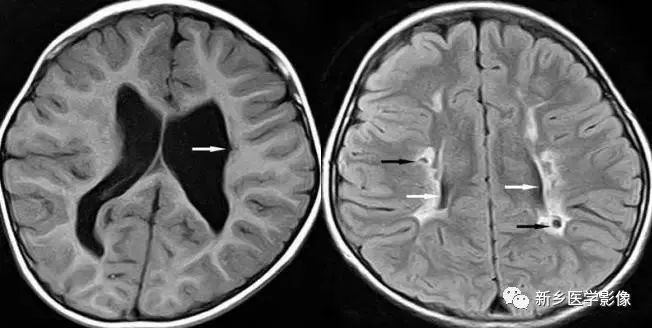

脑裂畸形:

脑裂畸形发生在胚胎期神经元移行阶段。脑裂畸形可累及一侧或双侧大脑半球。脑裂畸形位于侧面,常累及中央前、后回区,偶尔位于大脑半球的其他部位。

脑裂畸形的裂隙可以很窄,裂隙两侧灰质紧密相贴,称闭合型;裂隙也可以很宽,中间为脑脊液,称分离型。

临床上脑裂畸形常表现有癫痫发作,其他神经系统症状可从很轻微到很严重.主要取决于脑裂畸形使脑组织缺损的严重程度。单侧闭合型脑裂畸形症状通常较轻,双侧分离型脑裂畸形症状较明显。